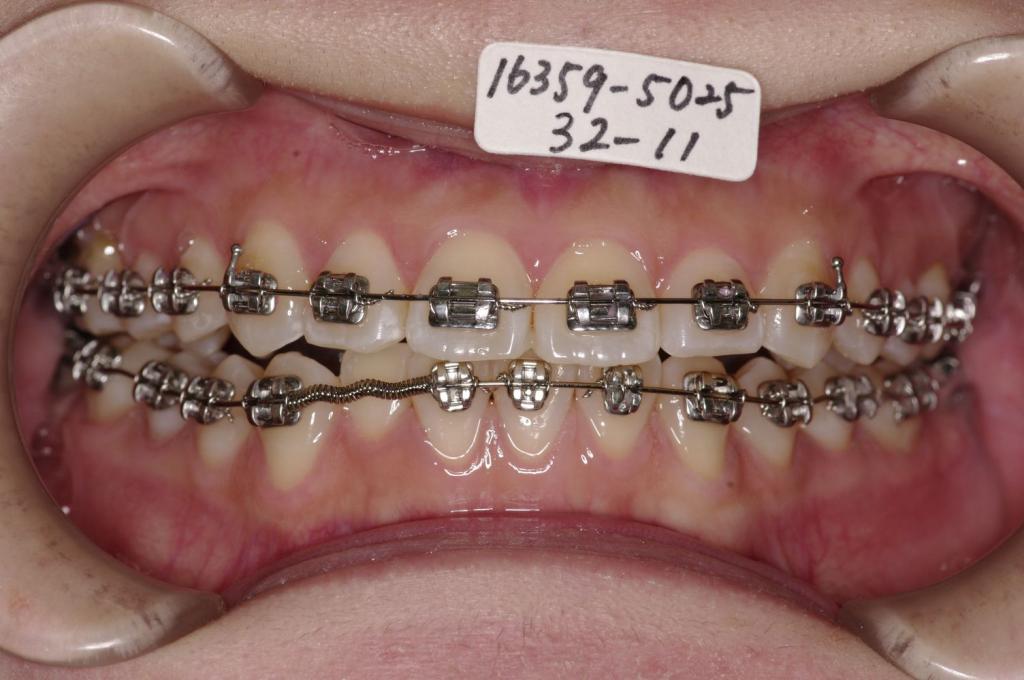

- 前歯、出っ歯・開咬の矯正治療

- 前歯が出ている